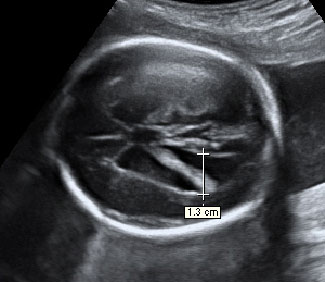

En esta imagen obtenida con una ecografía en 4D de un feto de 20 semanas de gestación se contempla cómo el bebé mueve sus brazos delante de su cara. Aún se encuentra muy delgado, ya que es a partir del tercer trimestre, sobre todo, cuando el feto empieza a acumular grasa bajo su piel.

Ecografía de bebé de 20 semanas de perfil

Podemos ver claramente los miembros superiores: el feto flexiona los brazos y los pasa por delante de la cara